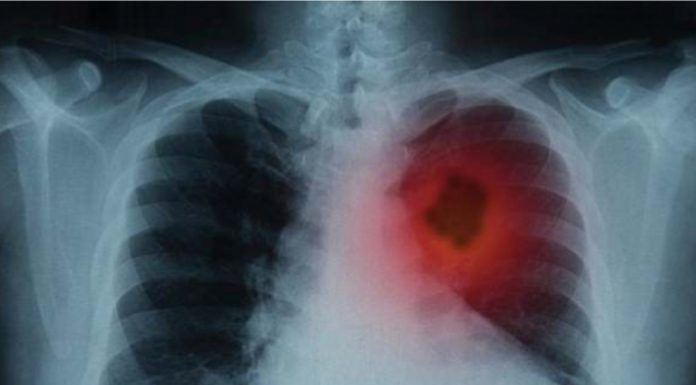

Çdo vit në botë vdesin 1.6 milion persona nga kanceri i mushkrive.

Duhanpirja dhe ndotja cilësohen si shkaqet kryesore të shfaqjes së kancerit në mushkri, ndërsa këtyre i shtohet edhe mënyra e të jetuarit.